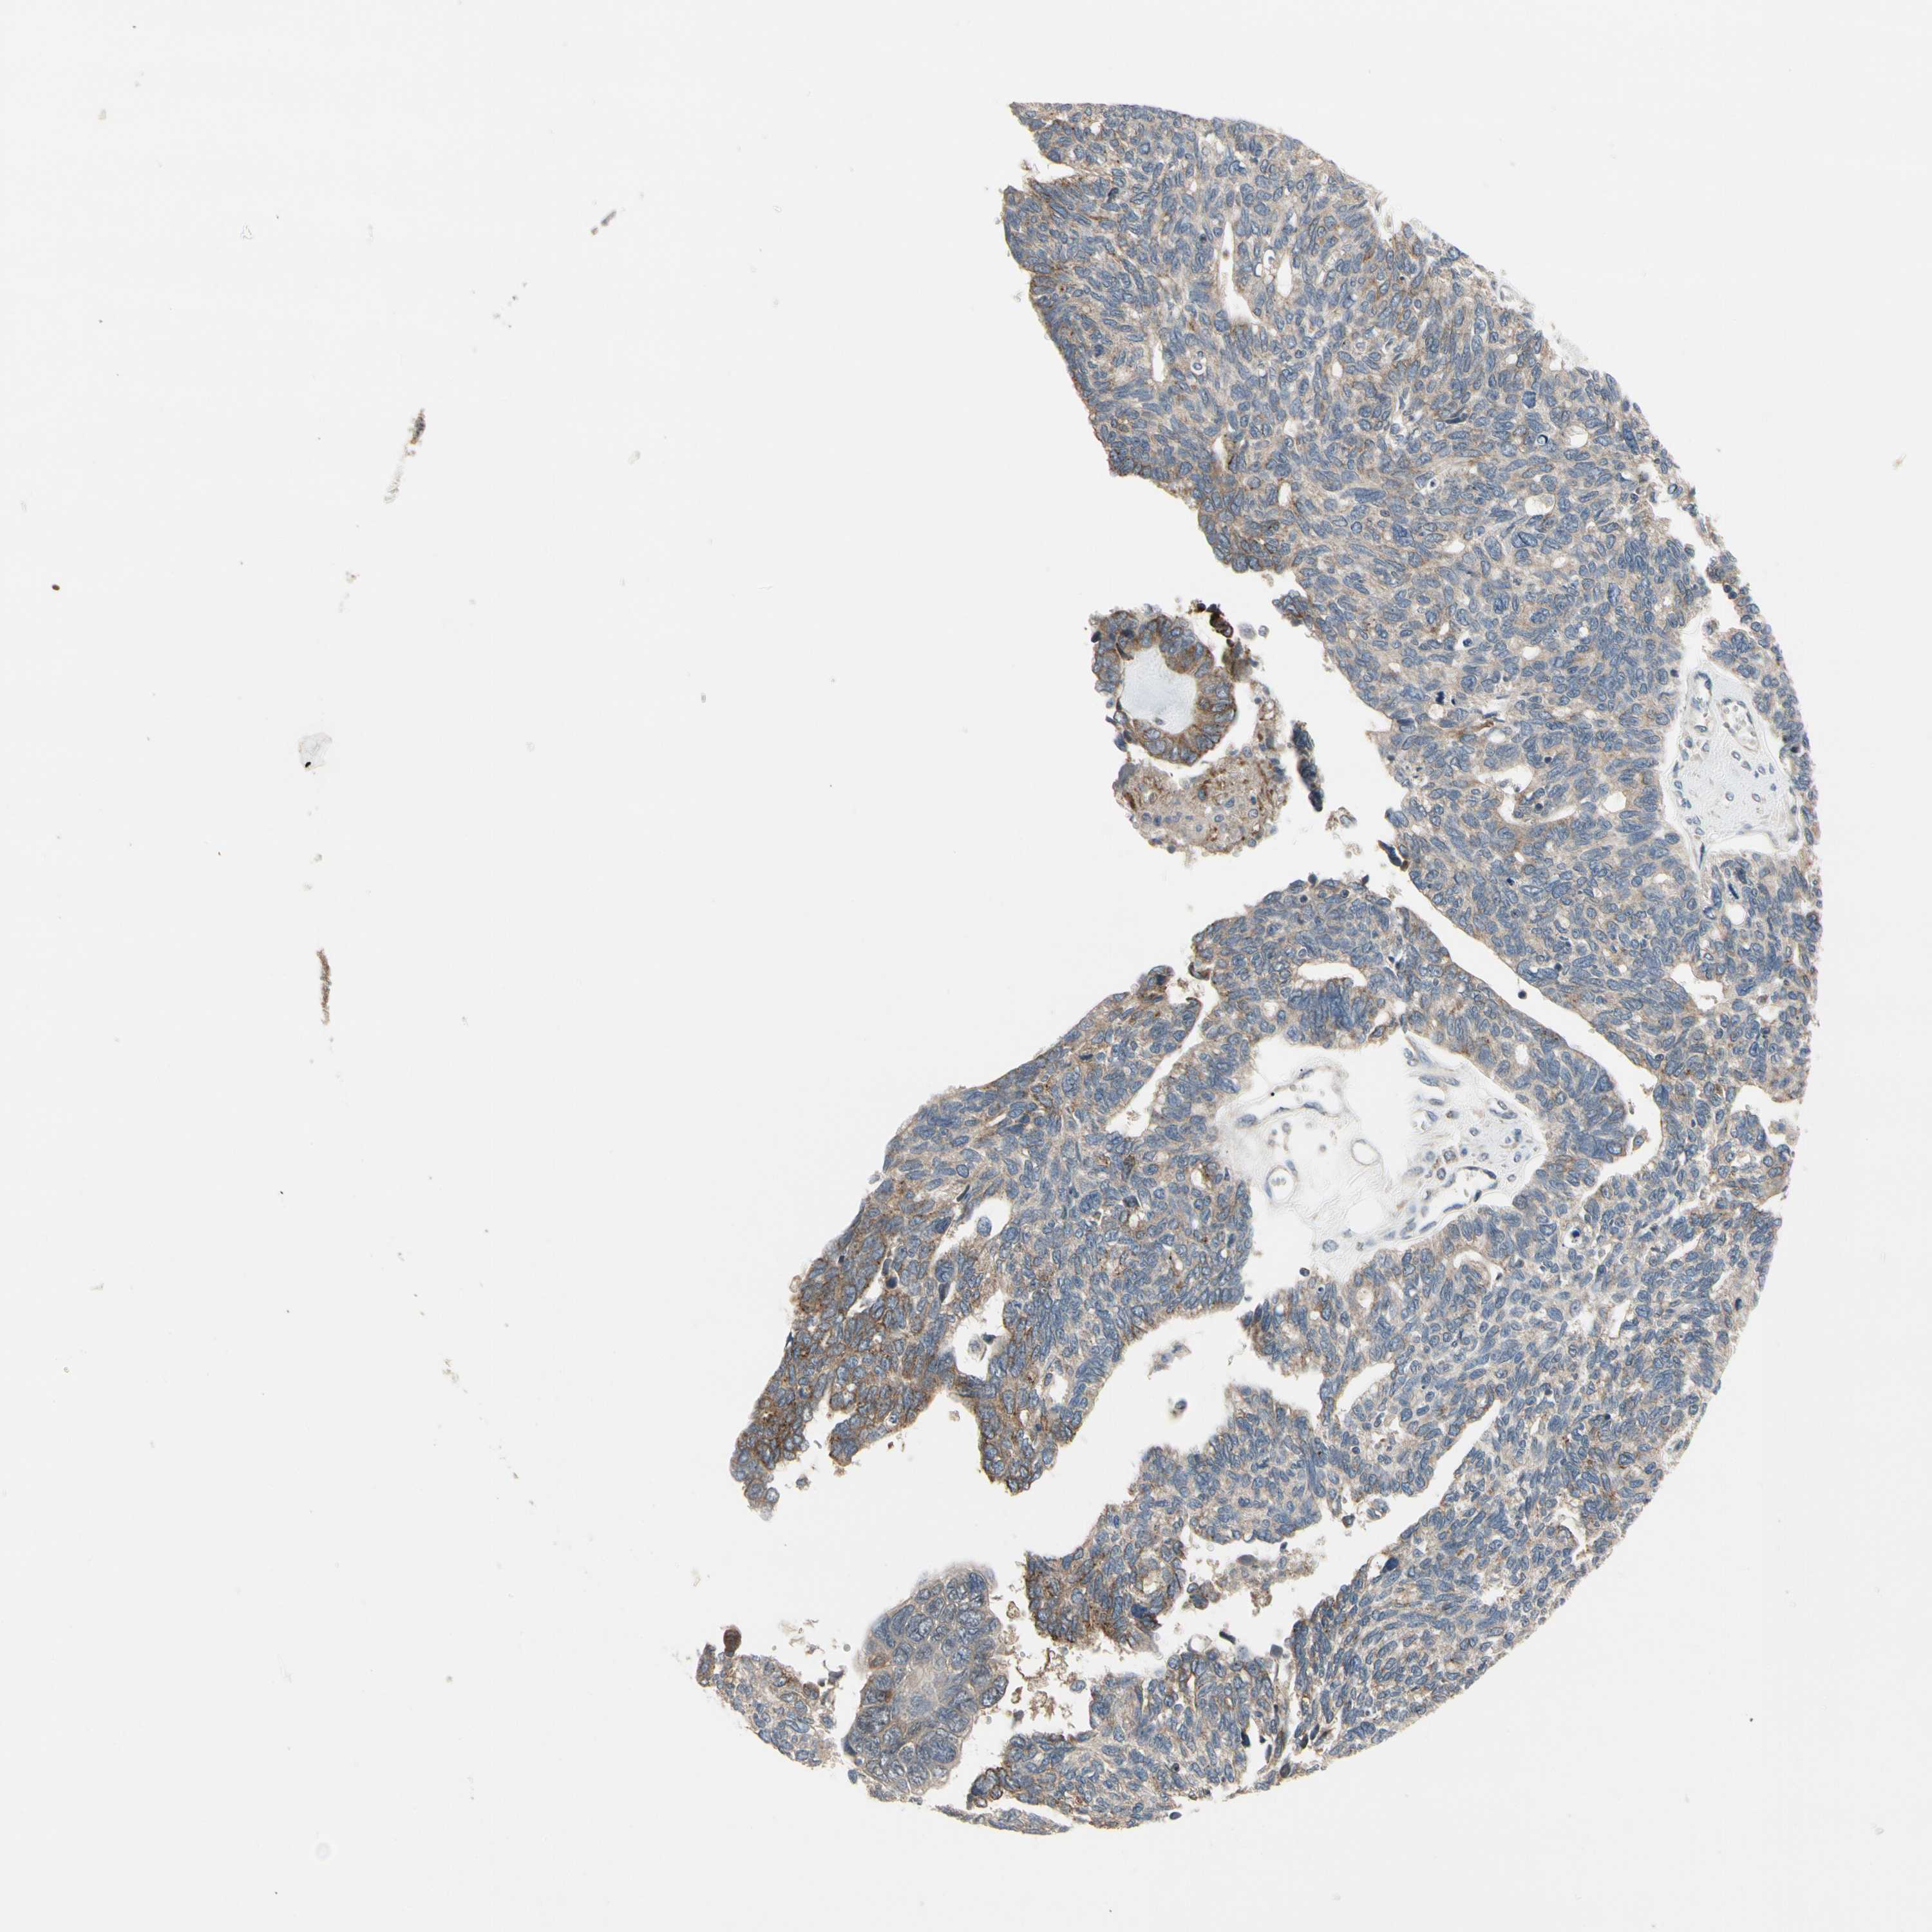

OVARIAN CANCER - Protein expressioni

A mouse-over function shows sample information and annotation data. Click on an image to view it in a full screen mode. Samples can be filtered based on level of antibody staining by selecting one or several of the following categories: high, medium, low and not detected. The assay and annotation is described here.

Note that samples used for immunohistochemistry by the Human Protein Atlas do not correspond to samples in the TCGA dataset.

Antibody stainingi

Antibody staining in the annotated cell types in the current human tissue is reported as not detected, low, medium, or high, based on conventional immunohistochemistry profiling in selected tissues. This score is based on the combination of the staining intensity and fraction of stained cells.

Each image is clickable and will lead to virtual microscopy that enables deeper exploration of all samples and also displays staining intensity scores, fraction scores and subcellular localization as well as patient and tissue information for each sample.

Antibody HPA008241

Staining

High

Medium

Low

Not detected

Intensity

Strong

Moderate

Weak

Negative

Quantity

>75%

75%-25%

<25%

None

Location

Nuclear

Cytoplasmic/membranous

Cytoplasmic/membranous,nuclear

Cystadenocarcinoma, serous, NOS

Carcinoma, endometroid

Cystadenocarcinoma, mucinous, NOS

Carcinoma, NOS